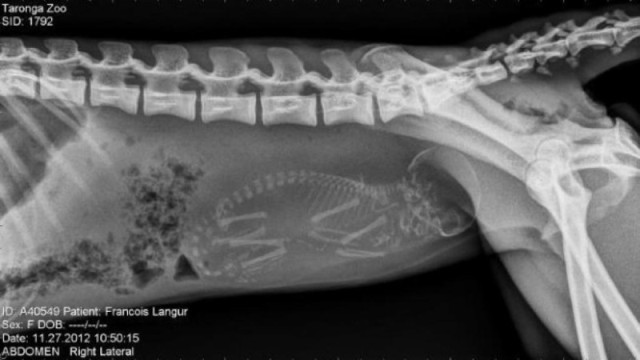

Մենք բոլորս լավ պատկերացնում ենք, թե ինչպես է անցնում մարդու հղիությունը, և շնորհիվ ժամանակակից տեխնոլոգիաների՝ կարող ենք տեսնել երեխային մայրիկի արգանդում հղիության ամենավաղ փուլում։ Իսկ ինչպե՞ս է ընթանում կենդանիների հղիությունը։ Մասնագետները, ովքեր հոգ են տանում հղի կենդանիների մասին, ներկայացրել են նրանց ռենտգենային և ուլտրաձայնային լուսանկարները, որոնք ձեր դատին է հանձնում «twizz.ru» կայքը։

Կապիկ